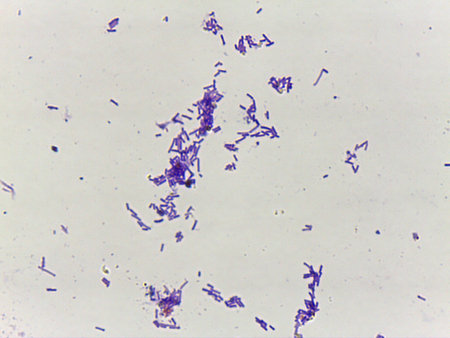

Title: showing title: microscopic view of purple rodshaped bacteria and circular microorganisms in dark background. resolution use.

gram stian was show gram positive bacilli.

Dense Clumps of Rod-Shaped Bacteria (Bacilli) Under a Microscope